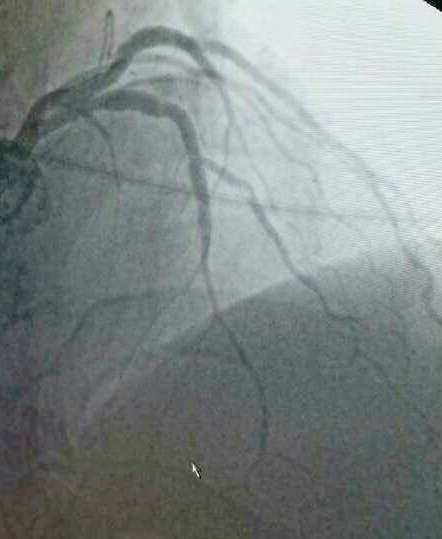

CRT-D植入术后,蔡文平主任又为一名冠脉支架植入术后患者进行了冠脉造影复诊,并指导科室医护人员为另一例放置双腔起搏器的患者进行了起搏器定期程控。陇南市第一人民医院心内科二病区自成立以来,在蔡文平主任的带领下,全体医护人员团结奋进、迎头赶上,不断学习先进的医学技术,在心血管介入治疗、电生理起搏治疗以及后期患者的复诊管理上逐步实现精准化、常态化、规范化,进一步缩小了与省内及周边发达地区同行之间的差距。

冠脉造影术中